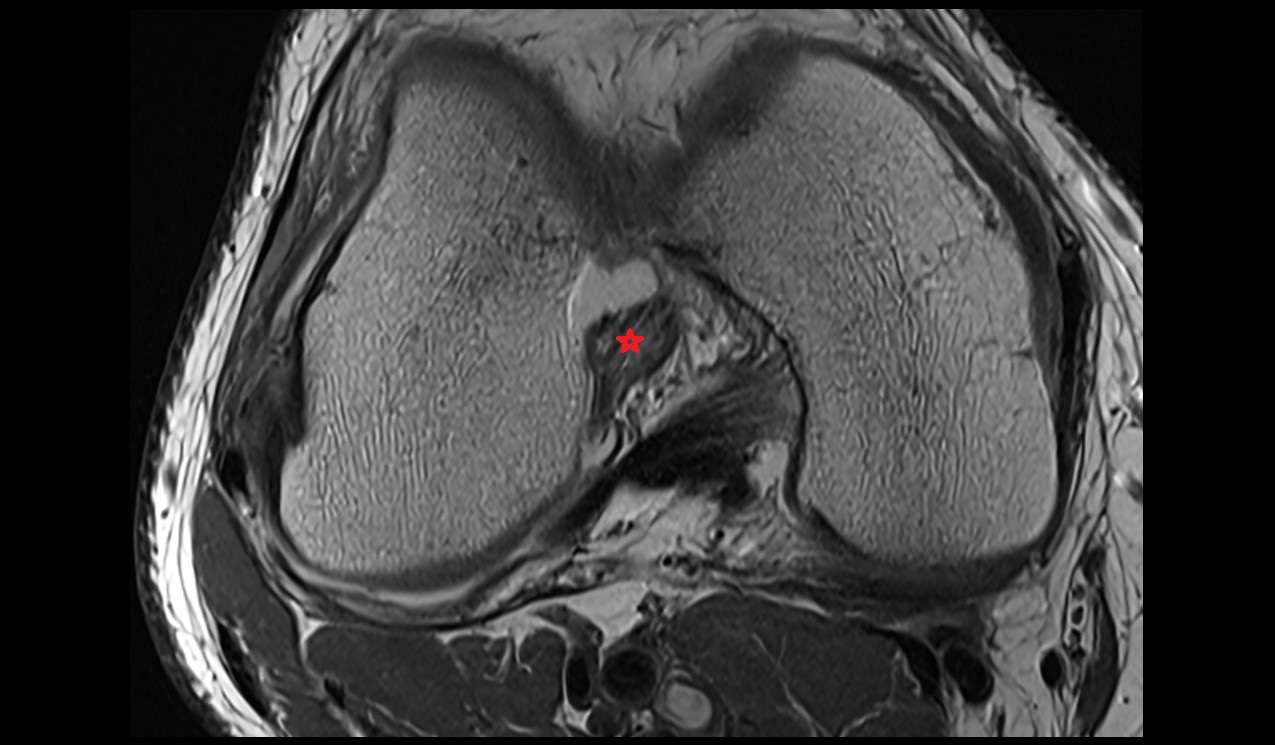

- Anterior cruciate ligament

- Posterior cruciate ligament

- Meniscus cartilage

- Medial meniscus

- Lateral meniscus